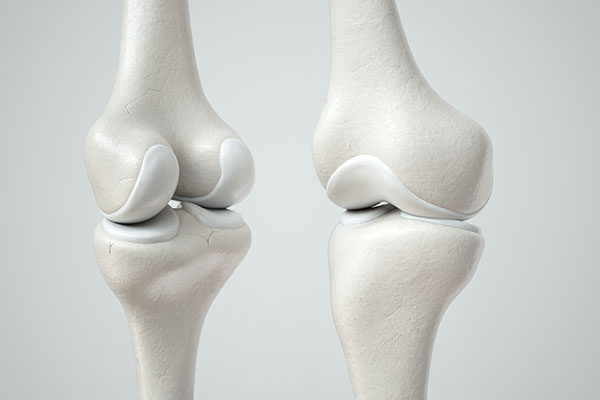

Układ kostno-stawowy